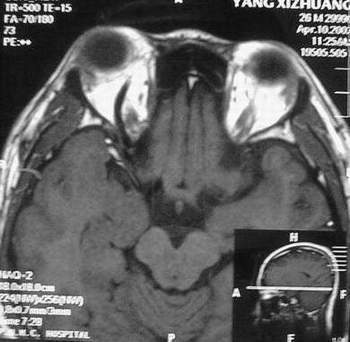

MRI及增强结果如下:

患者压颈及其它Valsava试验结果阴性。从MRI分析,在T1、T2、T+C检查该支血管均为明显流空现象,说明该血管血流速度很快,而从走行和分布看,眼上静脉可能性很大。也许也不能除外异常的眼动脉或异常血管。眶内主要可能的血管病变包括颈内动脉海绵窦瘘(高流窦)、AVM、眼眶静脉曲张、海绵状血管瘤、静脉性血管瘤、毛细血管瘤和眶内动脉瘤。。

1、颈内动脉海绵窦瘘:该患者临床有一部分支持该诊断。但从影像分析,海绵窦未见明显扩张;眼外肌未见明显充血扩张的长T1、长T2信号;颈内动脉海绵窦瘘常可见继发到血栓,可见到短T1、长T2的血栓信号。

3、AVM:患者目前的影像学资料尚不全面,但可符合该诊断。临床上改病常见于30岁左右年轻人,单侧发病,于本患较符合。问题在于临床没有明确的血管杂音,似乎难以解释。

纵上所述:本人觉得,患者AVM可能性较大,同时不能除外眶内动脉瘤。

关于进一步检查,我觉得DSA价格过于昂贵。是否可先进行彩色多普勒检查,首先可以明确是静脉系统还是动静脉瘘抑或是动脉瘤。第二步,可进行MRA检查,可以清楚地显示海绵窦地相关关系,并可借此诊断或排除颈内动脉海绵窦瘘。如还需第三部检查,可进行MRV检查,对静脉系统进一步评价。三种检查总共的费用2000多圆,但给予我们的信息量已经很丰富了。